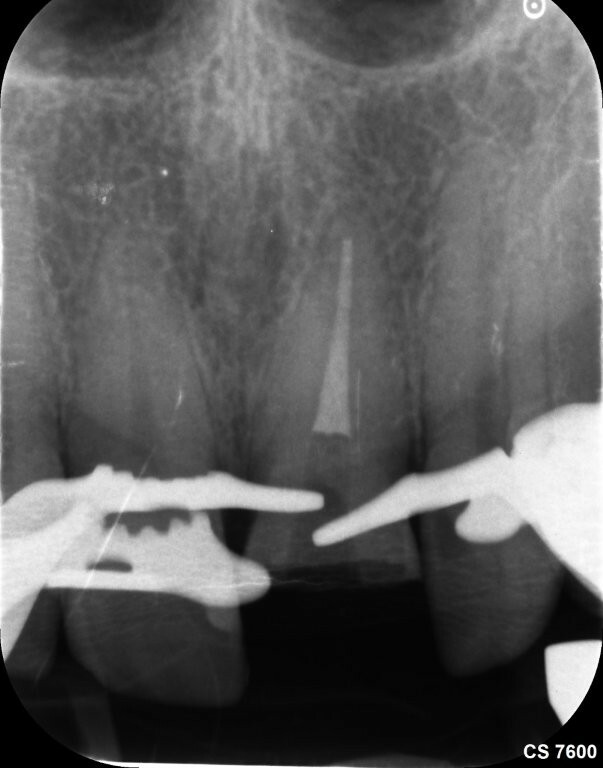

Das Zahnfragment hatte eine gute Passung auf den frakturierten Stumpf. So konnte im Vorfeld ein Silikonabdruck als Vorwall für den Kompositaufbau erstellt werden. Die endodontische Therapie sowie der Füllungsaufbau erfolgten ausschließlich unter dem hochauflösenden OP-Mikroskop (Zumax OMS2350). Die zu behandelnde Region wurde mit Ubistesin 1/200000 lokal betäubt. Anschließend wurde von 11 bis 22 ein Kofferdam angebracht. Der Zahn wurde mit einem konischen Diamanten trepaniert, die Trepanationsöffnung mit Gates-Glidden-Bohrern erweitert. Die Aufbereitung erfolgte mit dem Reciproc Blue System bis zur Größe 50.05.

Die Wurzelfüllung erfolgte in Continuus Wave Technik und Backfill in zwei Inkrementen mit

Guttapercha und AH Plus als Sealer. Anschließend wurden aufgrund der ovalen Kavität zwei Glasfaserstifte zur Stabilisation der Füllung eingebracht und mit Luxacore adhäsiv verklebt.